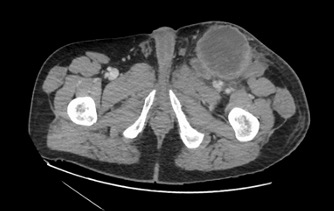

While the physical examination results were unrevealing for a definitive lesion consistent with primary cutaneous squamous cell carcinoma (SCC), the left inguinal nodules appeared consistent with metastatic SCC. This prompted further workup to better characterize the lesions and try to identify a primary neoplasm. Abdominal and pelvic computed tomography (CT) scans showed enlargement of the left inguinal lesion, appearing as a heterogeneous soft tissue mass measuring 11.2 × 7.4 cm, with adjacent smaller soft tissue masses extending slightly into the lower pelvis and multiple new enlarged lymph nodes vs masses (Figure 2). Results of a subsequent biopsy via interventional radiology confirmed the diagnosis of metastatic SCC. Results of a whole-body positron emission tomography (PET)/CT scan showed a metabolically active mass in the left groin.